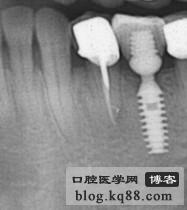

上頜是保留殘根覆蓋義齒,下頜是種植修復(fù),仔細(xì)看左上3側(cè)支根管被根充